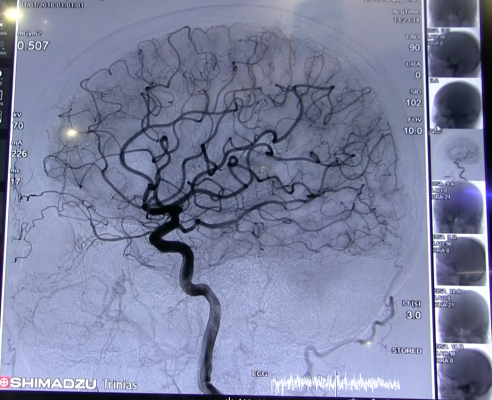

Frankel and his colleagues have been working for more than 25 years on testing innovative and new treatments to reduce the death and disability of this common disease. His team helped pioneer treatments in stroke including mechanical thrombectomy and intravenous tissue plasminogen activator, commonly called IV t-PA or alteplase.

Both are now a standard of care for patients with ischemic stroke who meet specific treatment criteria in the emergency setting. Ischemic stroke, caused by cerebral artery blockage, is the most common form of acute stroke.

Building on the success of Grady’s Marcus Stroke & Neuroscience Center in developing and testing the most cutting-edge treatments in acute stroke (e.g. mechanical thrombectomy), the new network is implementing innovative strategies to more rapidly identify patients with acute stroke in the field and directly transport them to the neuroangiography suite (aka “direct to angio”).

According to Raul Nogueira, M.D., professor of neurology at Emory University and director of Grady’s neuroendovascular service, “This approach substantially reduces the time from major arterial occlusion in the brain to definitive therapy with mechanical thrombectomy.” Nogueira said such approaches help minimize brain damage and promote recovery.